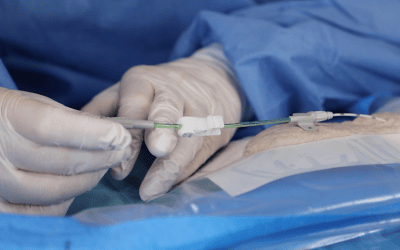

Actualmente, los reservorios, los catéteres Hickman, los PICCs, los catéteres centrales, los midlines y los catéteres cortos pueden venir con la característica “compatible con la alta presión” (llamada también CT rated o Power Injectable). Sin embargo, es fundamental comprobar siempre que nivel de alta presión y de alto flujo permiten para asegurarse que sean adecuados para la prueba que se quiera llevar a cabo.